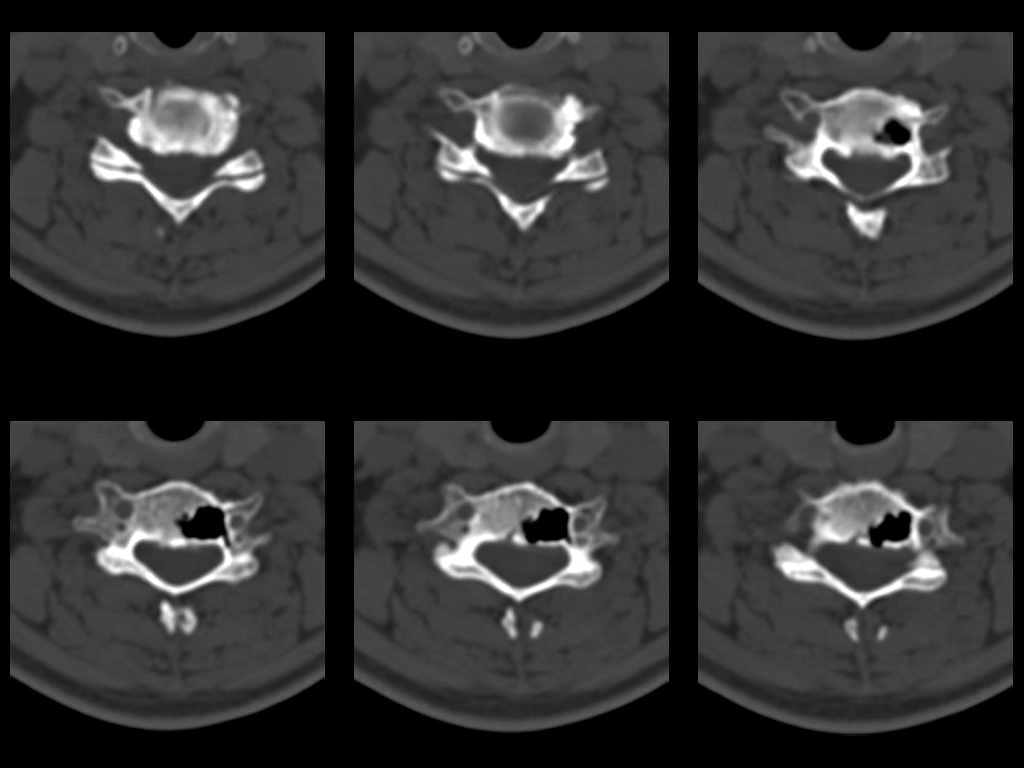

Участок деструкции в теле позвонка.

26 декабря 2002 г N1 26 декабря 2002 г N2 3 июня 2003 N1 3 июня 2003 N2

У женщины 49 лет, при рентгенографии шейного отдела в теле С6 выявлен участок деструкции. Часть N1

Больная находилась в неврологическом отделении с диагнозом энцефалопатия. Была проведена КТ тела С6, 26.12.2002 выявлен участок деструкции 0,9х1,2 см, плотность участка составляет -1022 ед.Н. аналогичная плотности воздуха в трахее.Возникает вопрос что это? Метастаз, киста, или какой то вредный анаэроб грызет тело позвонка? Через пол года 03.06.2003 произведено повторное исследование. Отмечается отрицательная динамика. Участок деструкции увеличился в размерах, увеличелась площадь разрушения задней поверхности тела С6.